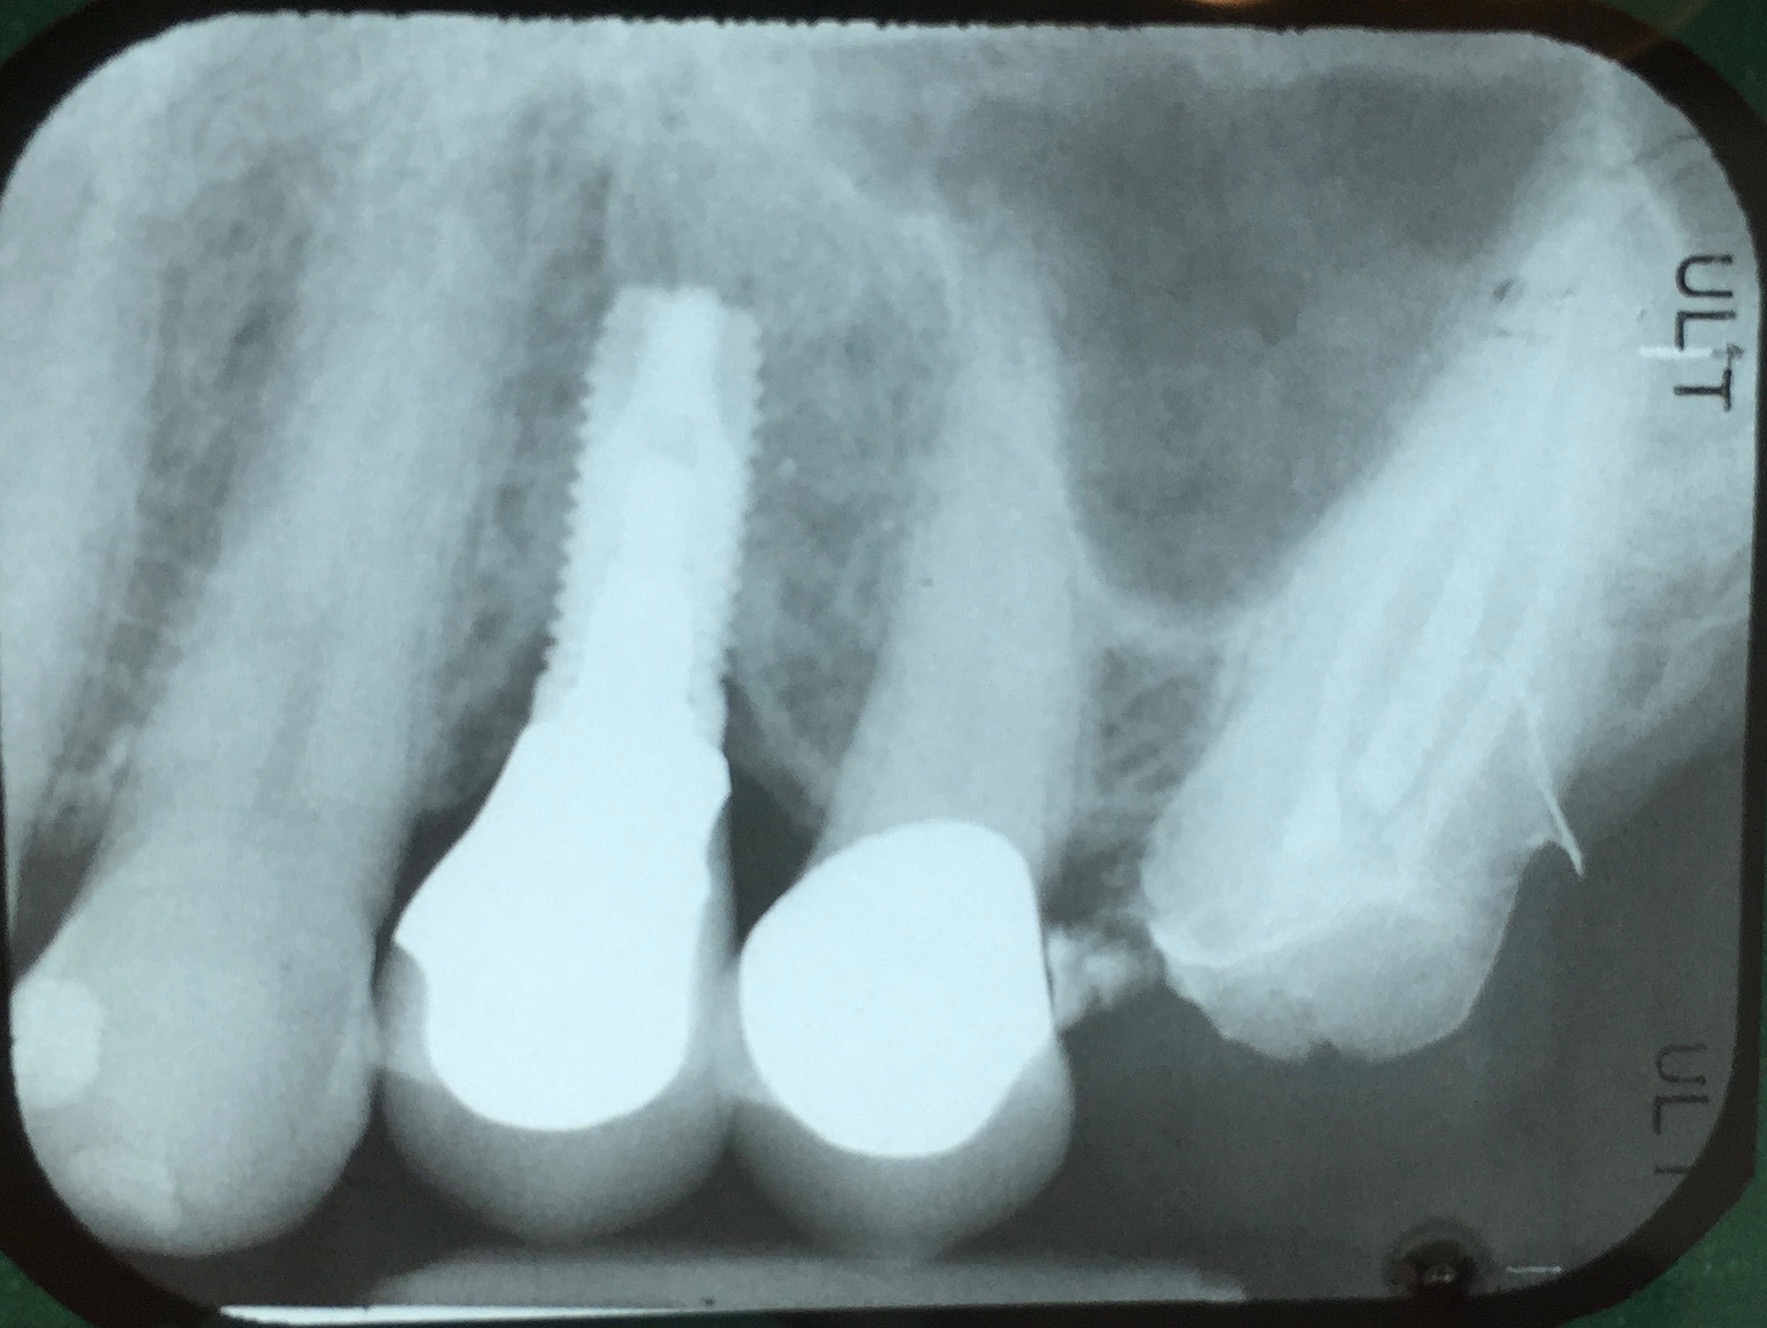

Fig 13. Radiograph depicting peri-implantitis.

Figure 13